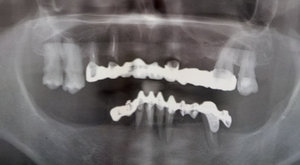

Обошла уже не одну клинику, везде говорят разные вещи. Кто говорит, что нужно чуть ли не все удалить и делать либо импланты, либо съемные протезы, кто — имплатны на низ, наверх металлокерамику, сроки и этапы работы все называют разные. Буду вам очень благодарна за консультацию. Снимок прилагаю.

Снимок не качественный, имеет множество затемнений, но и при этом могу вам сказать, что наверху удаляются исключительно корень и наклонившийся зуб. Все остальное остается и протезируется, далее необходимо установить импланты или, как альтернатива, бюгельный (замковый или кламмерный) или протез Кватротти. Все зависит от ваших финансовых возможностей.

Что делать с нижними зубами по снимку сказать сложно из-за затемнения, не хорошо виден костный рисунок. По срокам сказать сложно, необходимо ваше присутствие и качественный рентген-снимок. Что касается лечения и протезирования, это не более 30-40 дней.